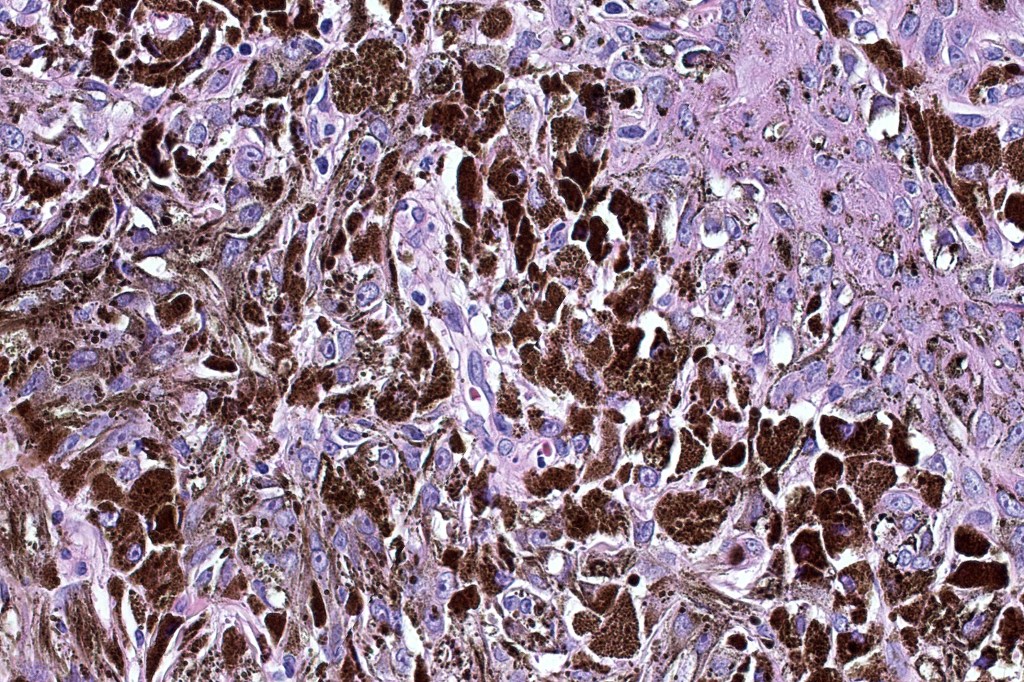

Combined common melanocytic nevus & BAP1-inactivated melanocytoma